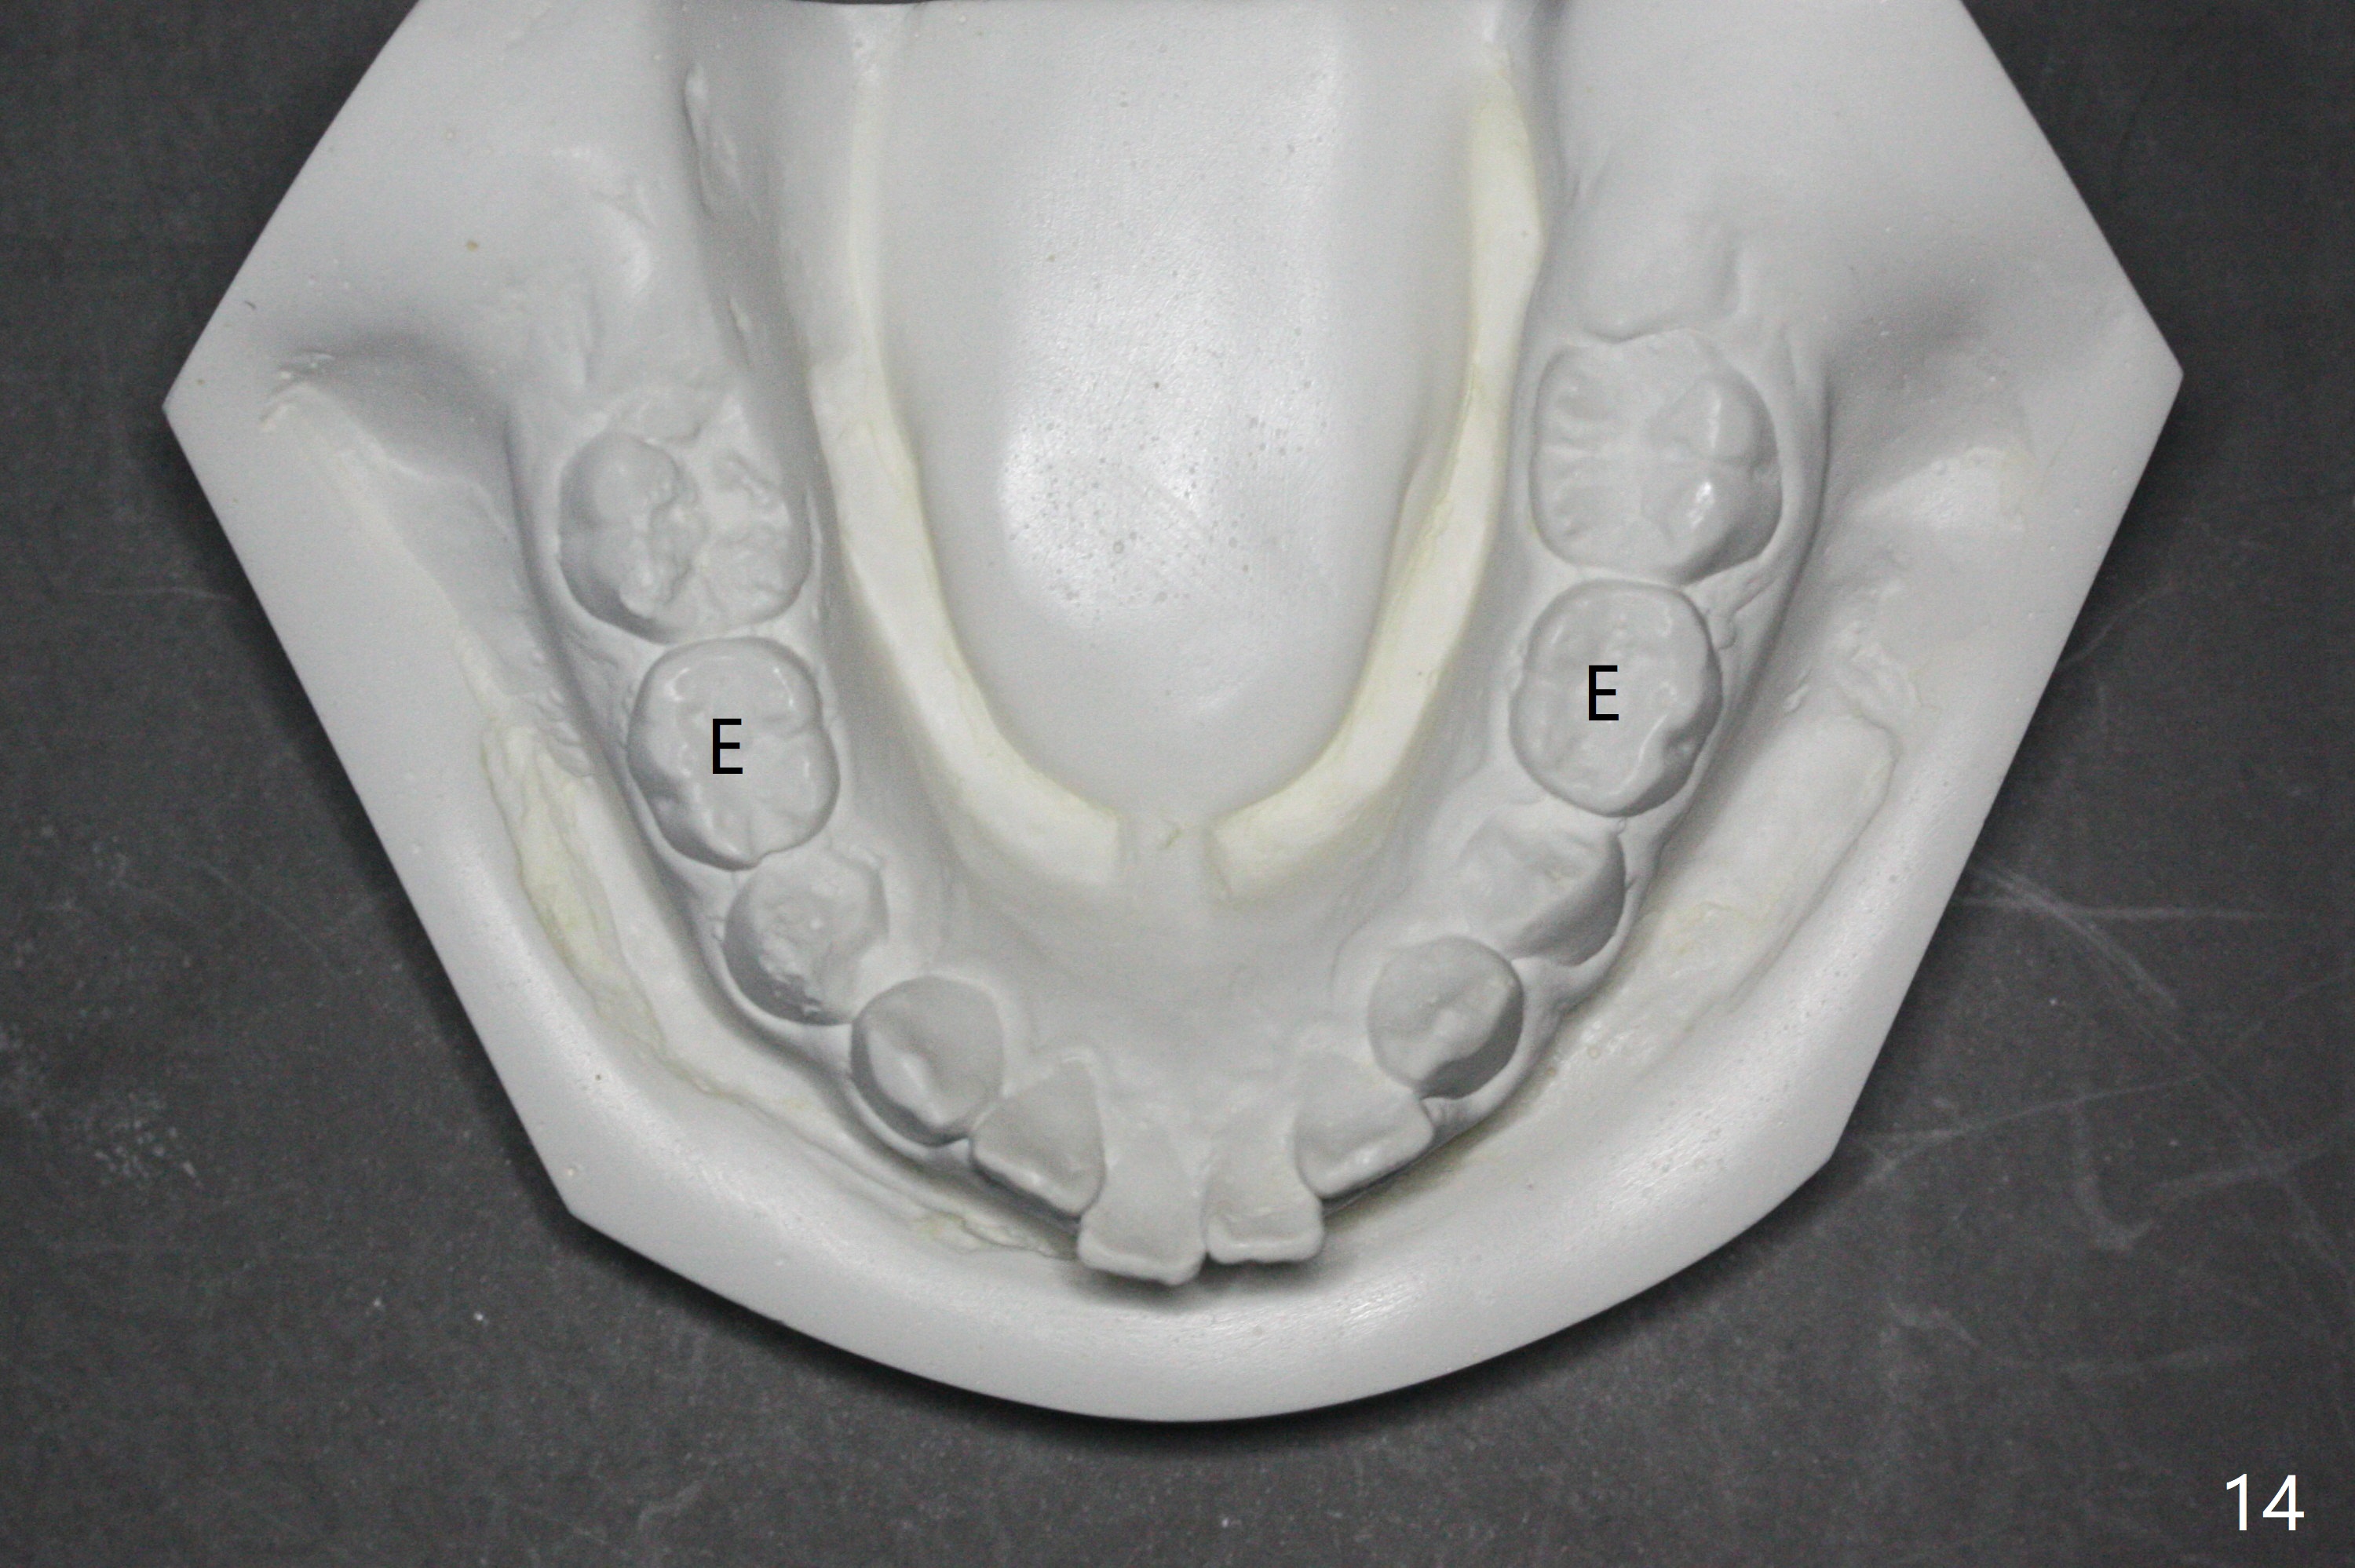

The mother of a 10-year-7-month old man requests treatment for the crowding lower incisors (Fig.14). The canines and molars are Class II by a half of a tooth (Fig.7,9,10,12). The dentition is mixed with E retention (Fig.13,14,16). Orthodontic treatment will start before E exfoliation for alignment and establishment of Class I occlusion as much as possible by distalizing U6s. Fine adjustment for intedigitation will be made when E exfoliate.